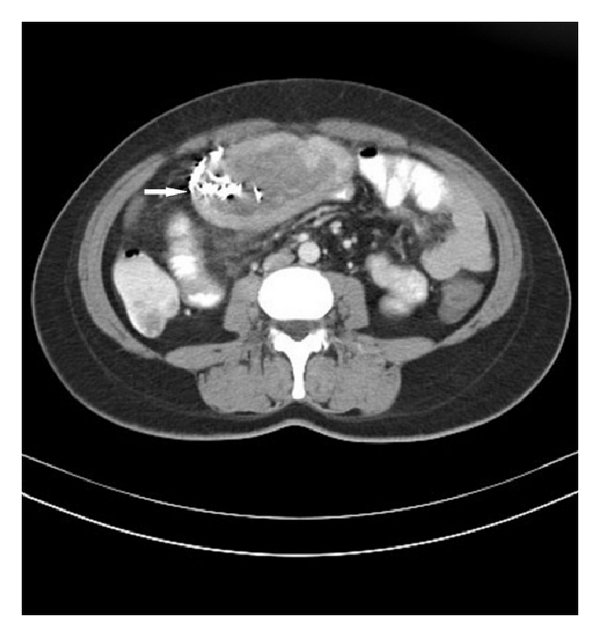

Gossypiboma and its Implications

1. Gossypiboma and its Implications Definition & Nomenclature Gossypiboma (also called textiloma) refers to a retained surgical sponge,